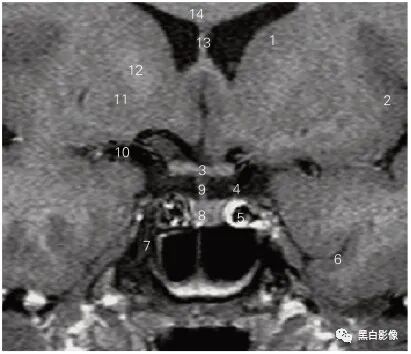

图5-1 经嗅球的冠状断层MR T1加权图像

1 嗅束沟 olfactory sulcus 2 嗅球 olfactory bulb

3 内直肌 medial rectus 4 鼻中隔 nasal septum

5 下直肌 inferior rectus 6 下鼻道 inferior nasal meatus

7 下鼻甲 inferior nasal concha 8 上颌窦 maxilary sinus

9 筛窦 ethmoid sinus 10 视神经 optic nerve

11 嗅池 olfactory cistern 12 眶回 orbital gyrus

13 直回 gyrus rectus 14 额叶 frontal lobe

15 大脑镰 cerebral falx